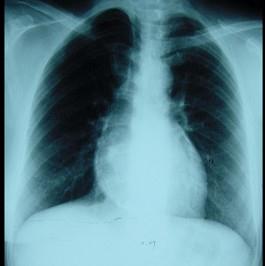

女性,46岁。间断胸痛4年,胸闷2年,外院诊断为“风湿性心脏病”。入院查体:血压110/65mmHg,颈静脉无充盈,心律75次/分,未闻及杂音,双下肢浮肿...

问题 女性,46岁。间断胸痛4年,胸闷2年,外院诊断为“风湿性心脏病”。入院查体:血压110/65mmHg,颈静脉无充盈,心律75次/分,未闻及杂音,双下肢浮肿,肝脏肋下2cm。 诊断明确后应尽早手术,围术期要点为 ( )